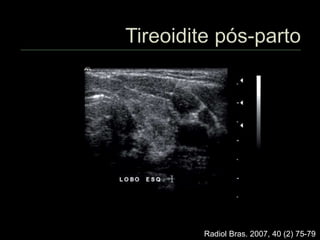

 Características semelhantes à De

Quervain

 Sem dor

 Hipertireoidismo, geralmente transitório

 Eventualmente necessita tratamento com

drogas antitireoideanas

 Fases tardias – sinais de fibrose

 Pode evoluir para hipotireoidismo

 4 a 7% das puérperas

 Provável etiologia autoimune

 Redução difusa da ecogenicidade

 Focos hipoecogênicos mal delimitados

esparsos

 Hiper ou hipotireoidismo transitório

 10 a 30% evoluirão para hipotireoidismo

permanente

Radiol Bras. 2007, 40 (2) 75-79